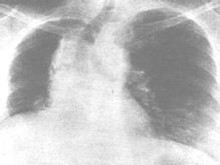

放射性肺炎(radiationpneumonitis)系由于肺癌、乳腺癌、食管癌、惡性淋巴瘤或胸部其他惡性腫瘤經(jīng)放射治療后,在放射野內的正常肺組織受到損傷而引起的炎癥反應。輕者無癥狀,炎癥可自行消散;重者肺臟發(fā)生廣泛纖維化,導致呼吸功能損害,甚致呼吸衰竭。

• 應該做哪些檢查項目呢?X線平片